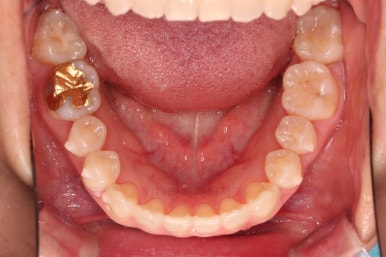

삐뚤한 덧니를 가지런하게 하기 위해서 필요한 부분의 어금니를 순차적으로 뒤로 밀어줍니다.

자세히 보면 치아 사이사이에 틈새가 생기는게 보이죠?

틈새를 일부러 만들어 해당 공간으로 덧니를 가지런하게 하는 원리입니다.

철사교정과 마찬가지로 앞니쪽에 유지장치를 구성하고 치료를 종료합니다.

매우 가지런해졌고요.

맞물림도 좋아졌고, 중앙선도 잘 맞춰졌습니다.